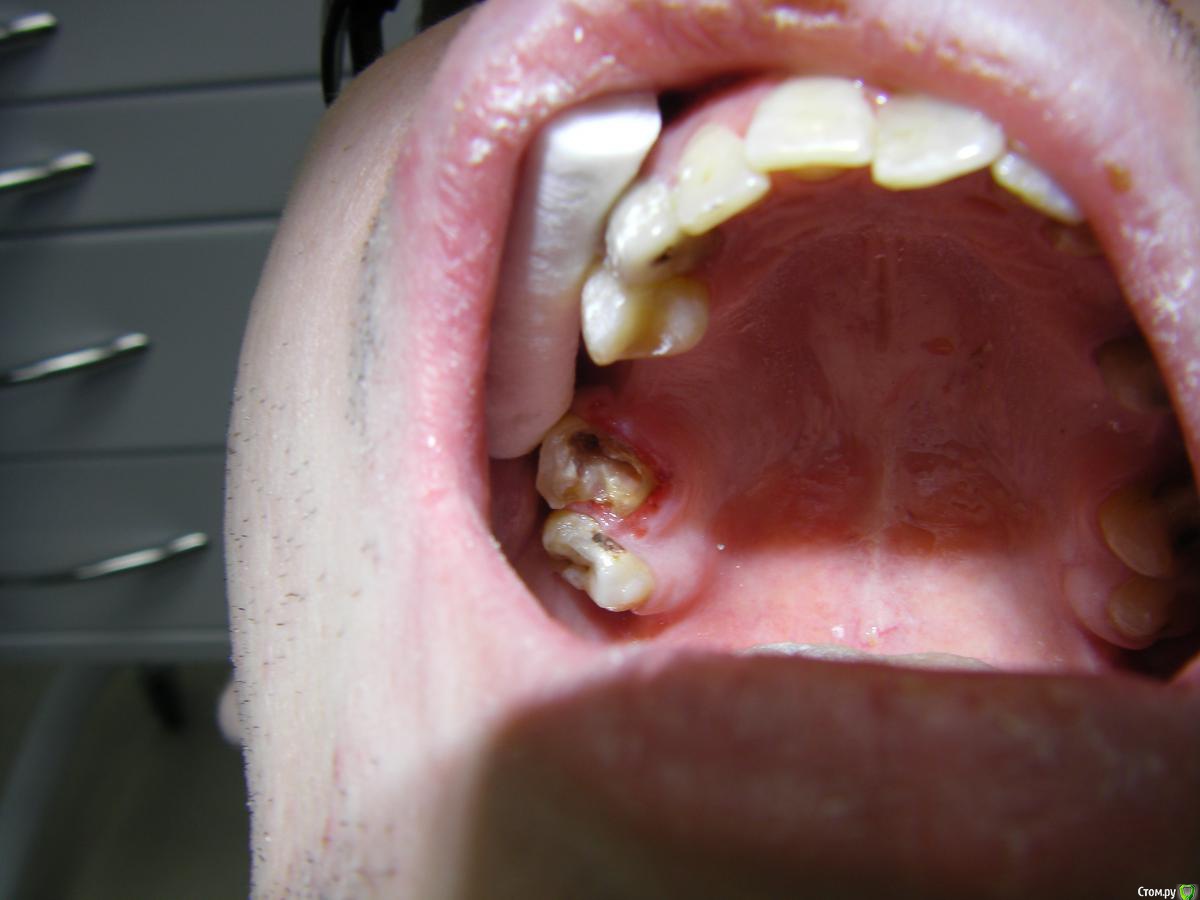

ARislanV Опубликовано 24 июня, 2016 Поделиться Опубликовано 24 июня, 2016 Лечу зуб 17 Pt, хотелось бы удлинить клиническую коронку зуба, что бы можно было поставить вкладку+ коронку одиночную. Что можно сделать посоветуйте пожалуйста? Ссылка на комментарий

Fred Опубликовано 27 июня, 2016 Поделиться Опубликовано 27 июня, 2016 Какой удалить, тут еще тканей полно! На такой зуб кламмер еще цепляется! У нас спасают такие же, но с двухмиллиметровым поддесневым поражением с 3 сторон.Руки бы хирургам поотрывать за удаление таких 1 Ссылка на комментарий

krasnyi Опубликовано 28 июня, 2016 Поделиться Опубликовано 28 июня, 2016 Какой удалить, тут еще тканей полно! На такой зуб кламмер еще цепляется! У нас спасают такие же, но с двухмиллиметровым поддесневым поражением с 3 сторон.Руки бы хирургам поотрывать за удаление таких +100 Я бы тоже не удалял. Ссылка на комментарий

krasnyi Опубликовано 28 июня, 2016 Поделиться Опубликовано 28 июня, 2016 Даже не заморачиваясь с десной можно изготовить вкладку с последующим протезированием. А удалить всегда успеете Ссылка на комментарий